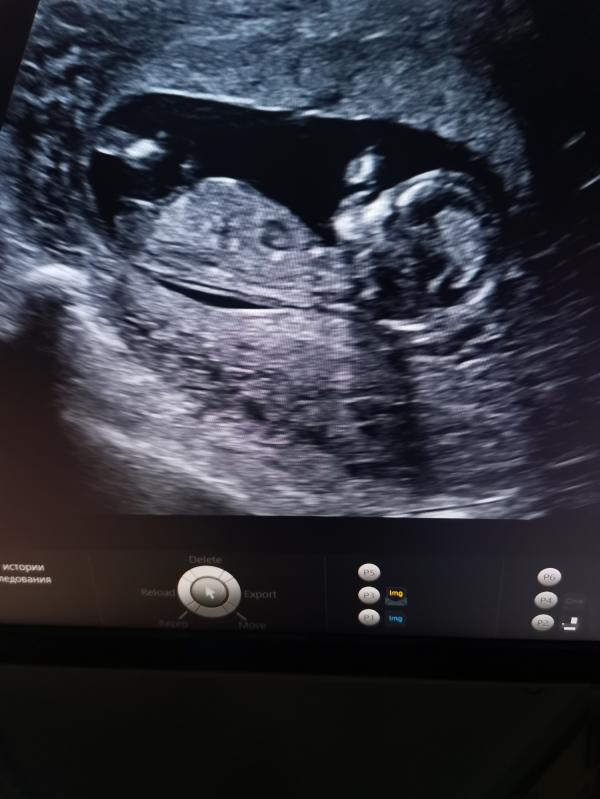

Оставлю это здесь на память 😀Наш первый скрининг, срок 12+6. Очень переживала по поводу этого дня. На УЗИ сказали всё хорошо, скорее всего девочка. Во время УЗИ подпрыгивает в животике, так радостно было на душе, мне кажется у меня улыбка до ушей была🤗